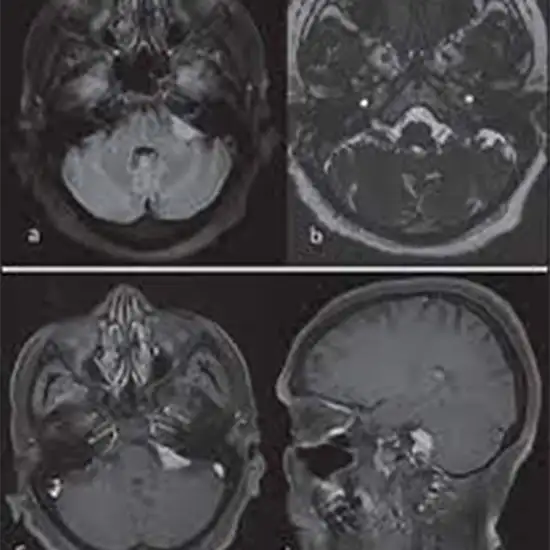

MRI Brain CP Angle with Contrast is utilized to evaluate the cerebellopontine angle, a spinal fluid-filled region. Its medial limit is the brain stem, its roof, the posterior barrier, is the cerebellum, and its lateral boundary is the posterior surface of the temporal bone. Therefore, the contrast enhances the MRI scan's sensitivity and diagnostic accuracy by improving the internal organs' visibility.

The physician suggests this test to diagnose traumatic brain injury (TBI), detect the presence of a stroke, and see if there is a brain tumor.